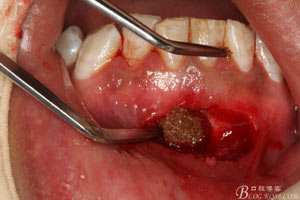

1.患者術(shù)前的口內(nèi)照片:31唇側(cè)有一膿瘺。捫診溢膿。

圖8.超聲骨刀去除根尖周?chē)腥竟琴|(zhì)

圖9.清晰可見(jiàn)牙膠從31根尖1/3溢出。